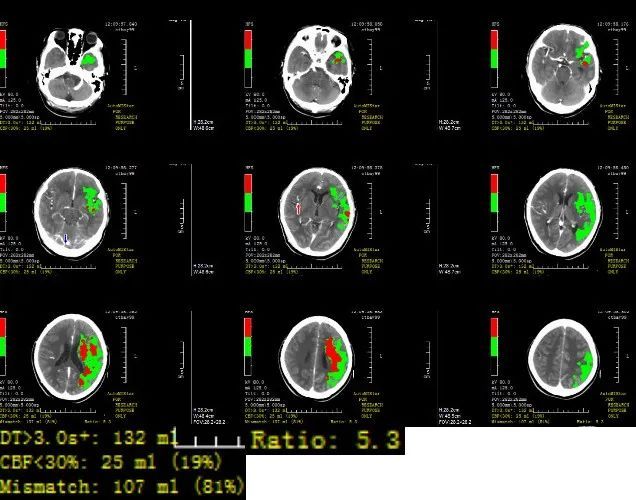

CTP:

脑血管造影情况:右侧股动脉穿刺,穿刺至发病时间5.33小时。行全脑血管造影示:左侧大脑中动脉急性闭塞,左侧大脑前动脉、大脑后动脉通过脑膜支代偿左侧大脑中动脉供血区,并逆流至M1远端。

在泥鳅导丝、V18支撑导丝导引下,8F导引导管直接进入左颈内动脉C1近段,取5F的Navien中间导管,置于颈内动脉岩骨段,取可操纵微导丝在微导管辅助下小心通过血栓闭塞段到大脑中动脉M1,微导管通过闭塞段后回撤至颈内动脉末端,手推造影剂提示左侧大脑中动脉可见前向血流通过闭塞段,首过阳性,考虑左侧大脑中动脉慢性狭窄基础上急性闭塞,予替罗非班0.75mg静脉符合,并0.3mg/h持续静脉泵入维持;微导管在微导丝辅助下送大脑中动脉M1段以远,退出微导丝,将(4.0*25 NeuroHawk®取栓支架)在透视下放入左侧大脑中动脉M1段并释放支架取栓,支架打开欠满意,约5分钟后予撤出支架及微导管,此过程中50ml注射器保持负压抽吸血液,取出一个血栓,大小约0.2cm×0.5cm。

复查造影提示左侧大脑中动脉再通,残余重度狭窄,远端血流可,未见血栓异位栓塞,mTICI分级3级(穿刺至再通时间1.07h)。行DynaCT见左侧额叶、顶叶皮质少许高密度灶,观察18分钟复查造影提示血管狭窄无回缩,结束手术,未中和肝素,保留右股动脉鞘,局部无菌纱布予覆盖并加压包扎。术后患者镇静状态,双侧瞳孔等大,疼痛刺激左侧肢体无活动。患者左侧大脑中动脉经支架取栓完全再通。

术后30小时随访:NIHSS评分8分,CT未见大面积脑梗等情况。

术后7天随访:NIHSS评分1分。

术后90天随访:mRS评分1分。